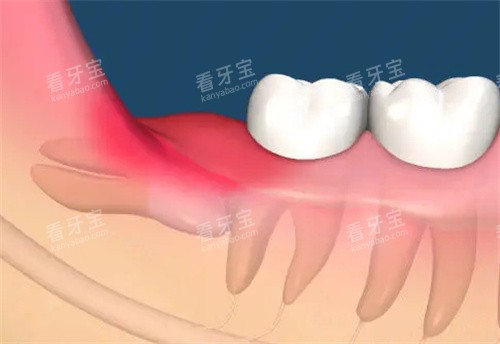

反复发作的智齿冠周炎(每年发作≥3次)。

智齿本身龋坏且已波及牙髓。

阻生智齿压迫邻牙导致牙根吸收。

智齿引发颌骨囊肿或含牙囊肿。